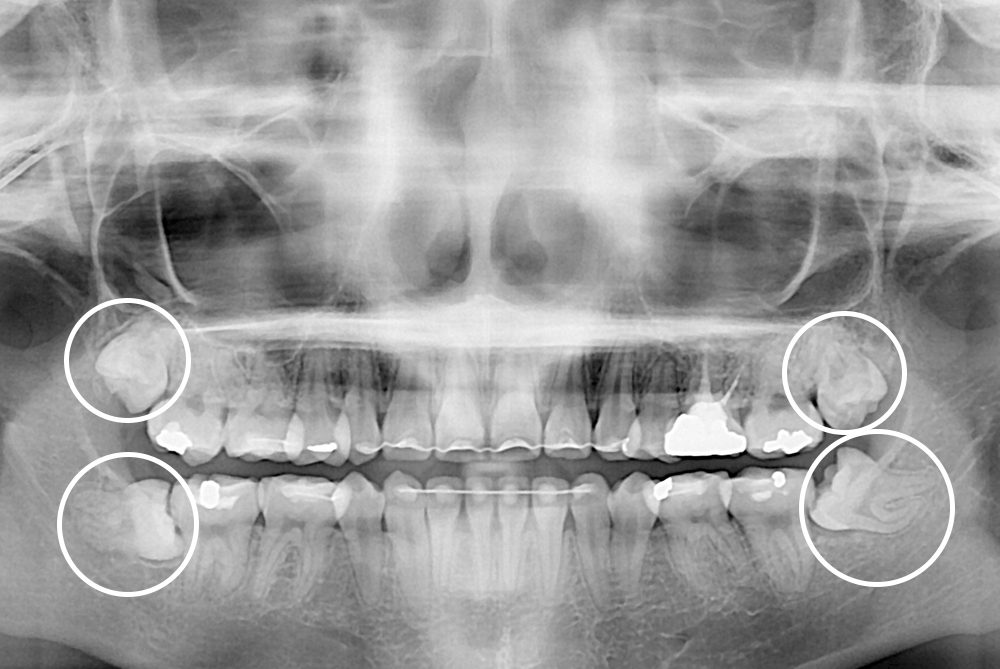

[사랑니] 매복 사랑니 발치

치료전 : 2019-07-02